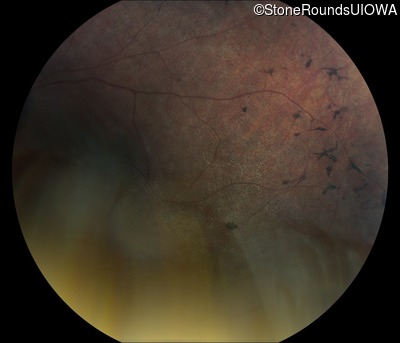

Fundus Photography - Right - No Light Perception

Exemplar